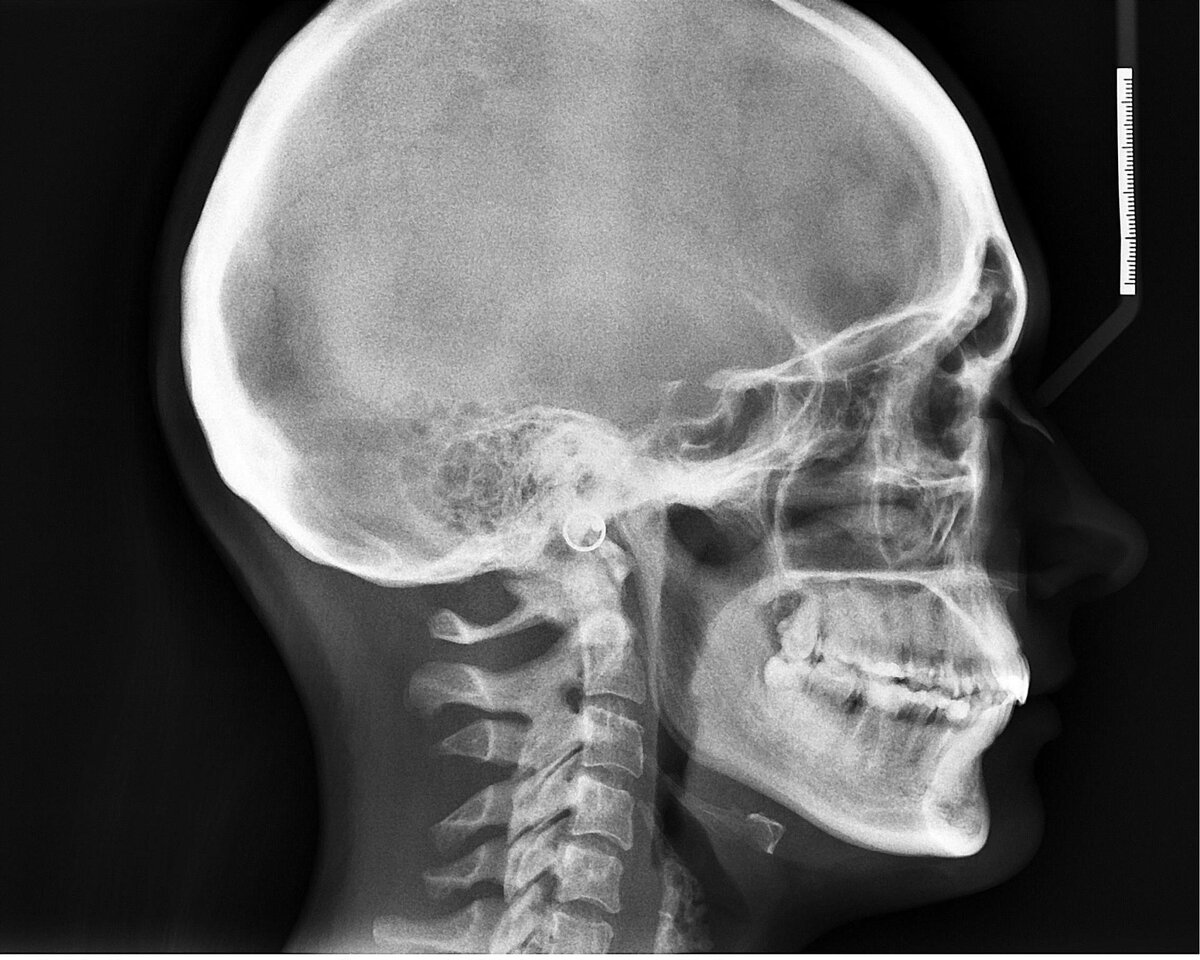

В 1895 году немецкий физик Вильгельм Рентген работал с катодно-лучевой трубкой. Несмотря на то, что сама трубка была экранирована, Рентген заметил, что картон, покрытый платиносинеродистым барием и находившийся рядом с трубкой, начинал светиться в темной комнате.

Рентген попытался блокировать лучи, но большинство вещей, которые он помещал перед ними, проявляли аналогичный эффект. Когда в конце концов он поставил перед трубкой свою руку, то заметил, что она начинает просвечиваться на изображении, проецируемом на экране. Свое открытие он назвал «икс-лучами» (X-rays). После Рентген заменил трубку фотографической пластиной и получил первую рентгенограмму.

Вскоре после этого технология была адаптирована медицинскими учреждениями и исследовательскими лабораториями.